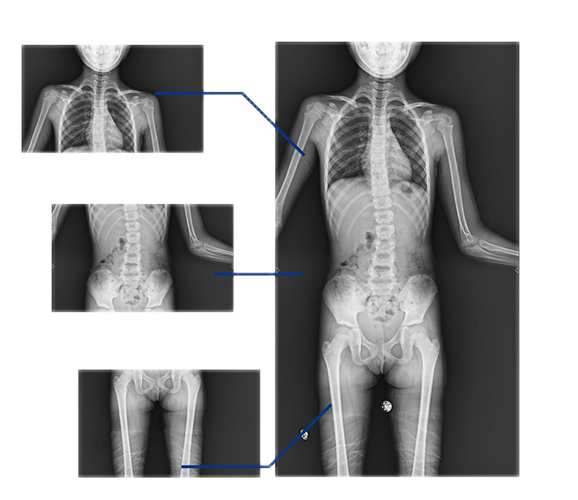

同時(shí),動(dòng)態(tài)DRF的全景拼接技術(shù)能夠輔助脊柱畸形矯形治療、康復(fù)檢查,為臨床提供高精度圖像。該技術(shù)可自動(dòng)或手動(dòng)拼接,圖像無拼接痕跡,全脊柱重組影像準(zhǔn)確率高、結(jié)構(gòu)清晰。在脊柱側(cè)彎患者的康復(fù)治療中,拼接技術(shù)的應(yīng)用還有助于臨床對(duì)患者的脊柱整體形態(tài)、病變程度等進(jìn)行全面而直觀地掌握,為后續(xù)的治療提供良好的支持。